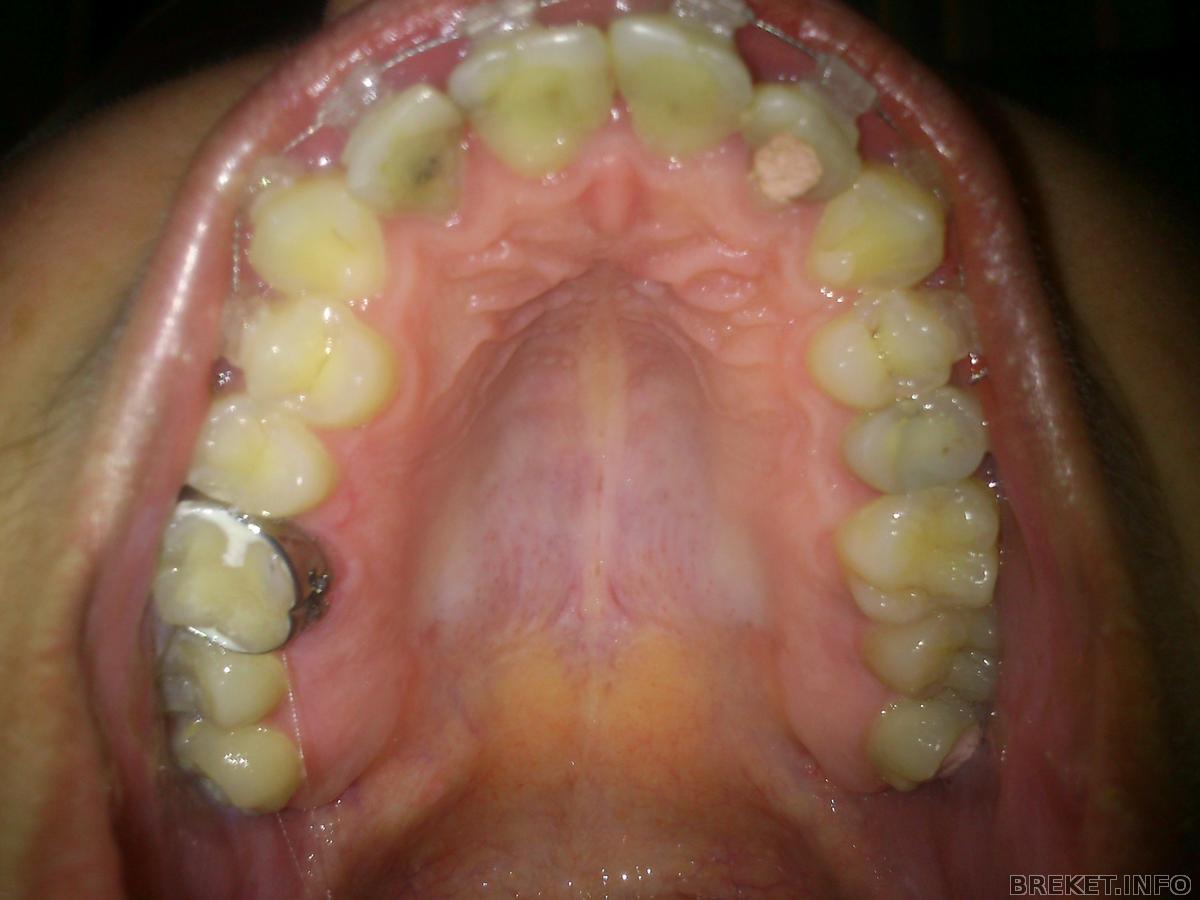

ПРивет всем! Начну издалека - в четверг у меня откололся кусок зуба и я записалась к своему терапевту на прием на пятницу утро (а вечером у меня установка) пришла вобщем все сделали и как обычно разговорились, терапевт у меня молодая девушка и у нее улыбка ну просто мечта любого из нас, таких ровненьких и беленьких идеальных зубов я не видела никогда, так вот я ей сказала что у меня установка вечером и что я сомневаюсь насчет ортодонта на что она сказала что сама ставила себе брекеты именно у этой женщины и что она супер пупер врач, дотор наук там профессор в университете преподает и тд и тп но просто она всегда сердитая и молчаливая, и что даже ей(моему терапевту) она особо не рассказывала план лечения ))) ну вот такая манера у доктора... поэтому я в конец расслабилась и решила довериться (ну вот такой я доверчивый человек).

Все прошло очень быстро и совершенно безболезненно. Я так и не поняла почему многие боятся расширителя??? когда мне наклеили ВЧ дали отдохнуть минут 5 потом принялись за НЧ доктор все делала сама и паралельно все рассказывала все то что я уже знаю от вас ))) про уход про еду про боли ))) короче чуство конкретной стянутости я почуствовала в тот же момент как она натянула дугу... сразу мне все понравилось и я ехала домой и постоянно улыбалась. По дороге домой очень жалела что в машине на панели нет маленького зеркальца ))) на каждом светофоре отворачивала зеркало заднего вида чтоб полюбоваться на свою "практически голливудскую улыбку" )))))))) заехала к подруге похвасталась она сказала что мне идет и с брекетами я выгляжу моложе, муж сказал "Думал будет хуже" теперь он мне должен новые туфли за такую оценку

поздравляю)) у вас очень крутой ортодонт, судя по всему... скоро будут очень красивые зубки!